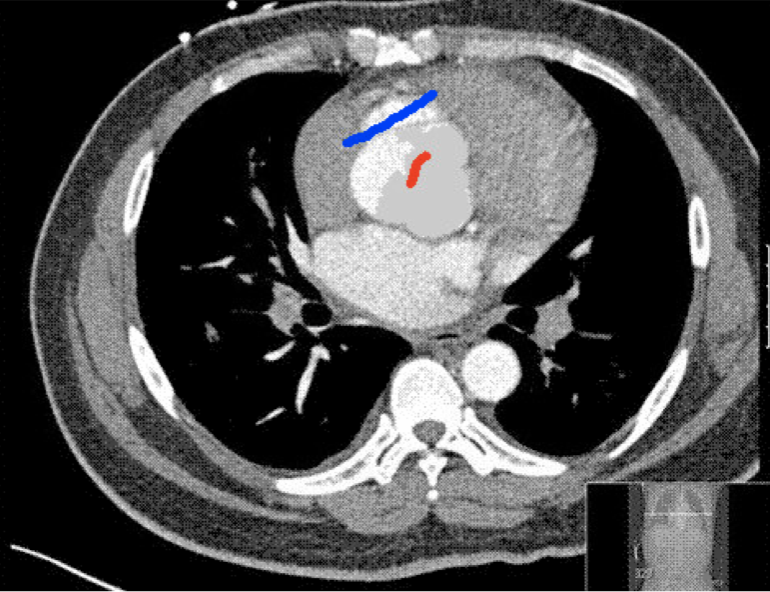

Four sets of test results are shown below. In Test 1 we compare models M1 – M6 to the proposed model M7 for two images which are hard to segment. The first is a CT scan from which we would like to segment the lower portion of the heart, the second is an MRI scan of a knee and we would like to segment the top of the Tibia. See Figure 9 for the test images and the marker sets used in the experiments. In Test 2 we will review the sensitivity of the proposed model to the main parameters. In Test 3 we will give several results achieved by the model using marker and anti-marker sets. In Test 4 we show the initialisation independence and marker independence of the Geodesic Model on real images.

Refer to captionRefer to captionRefer to captionRefer to caption

(i)                                 (ii)                                 (iii)                                 (iv)

Figure 9: Test 1 setting: (i) Image 1;  (ii) Image 1 with marker and anti-marker set shown in green and pink respectively;  (iii) Test Image 2; (iv) Image 2 with marker set shown.